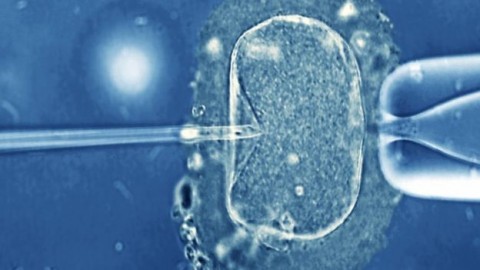

Basicamente, o processo é o seguinte. Dois óvulos são fertilizados, um da mãe e outro da doadora, com espermatozoide do pai. O núcleo dos embriões resultantes é retirado, e conserva-se somente o criado pelos pais. Este núcleo é introduzido no embrião da doadora, substituindo o núcleo descartado. E o embrião resultante é colocado no útero da mãe. É possível fazer a mesma coisa em escala ovular, antes da fertilização. Em ambos os casos, a mudança é permanente e a futura descendência do bebê que nascer com essa técnica também estará livre da doença mitocondrial.

No experimento, realizado com camundongos, os cientistas liderados por Tony Perry, do Departamento de Biologia e Bioquímica da Universidade de Bath, no Sudoeste da Inglaterra, usaram tratamentos químicos para ‘enganar’ óvulos e fazer com que eles começassem a se desenvolver em embriões sem terem sido fertilizados. Mas, com apenas metade do código genético necessário para formar um organismo, estes embriões haploides, conhecidos como partenotos, são inviáveis, morrendo em poucos dias. Antes disso, no entanto, os pesquisadores injetaram neles espermatozoides, fornecendo a segunda metade dos pares de cromossomos necessários para que continuassem a se desenvolver num ser diploide.